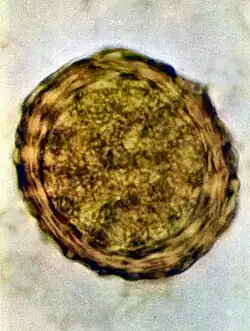

Os ovos tem a princípio cor branca, mas devido ao contato com os pigmentos biliares das fezes, adquirem um tom castanho, às vezes descrito como de amarelo-escuro a marrom.[9] Tem formato oval a redondo e medem 45 a 75 micrômetros (μm) de comprimento e 35 a 45 (ou 50, a depender da fonte)[10] μm de largura;[11] possuem uma cápsula espessa graças a membrana externa mamilonada, formada por mucopolissacarídeos e secretada pela parede uterina. Internamente a esta membrana, existe outra constituída de quitina e proteína. A mais interna é delgada e impermeável à água constituída de 25% de proteínas e 75% de lipídios. É a camada mais interna que garante ao ovo a capacidade de resistir às condições adversas do ambiente. Em seu interior, os ovos tem uma massa de células germinativas. É possível encontrar nas fezes humanas ovos inférteis de áscaris, isso ocorre quando a fêmea do verme não foi inseminada, ou quando está iniciando a oviposição.[10] Pode-se identificar ao microscópio esse tipo de ovo pois eles possuem o interior desorganizado, com citoplasma granuloso e sem estruturas visíveis.[9][11] A membrana mamilonada é mais delgada e são mais alongados que os ovos férteis, medindo 80 a 90 μm de comprimento. Algumas vezes, mesmo os ovos férteis podem não ter a membrana mamilonada, sendo chamados de ovos decorticados.[9]